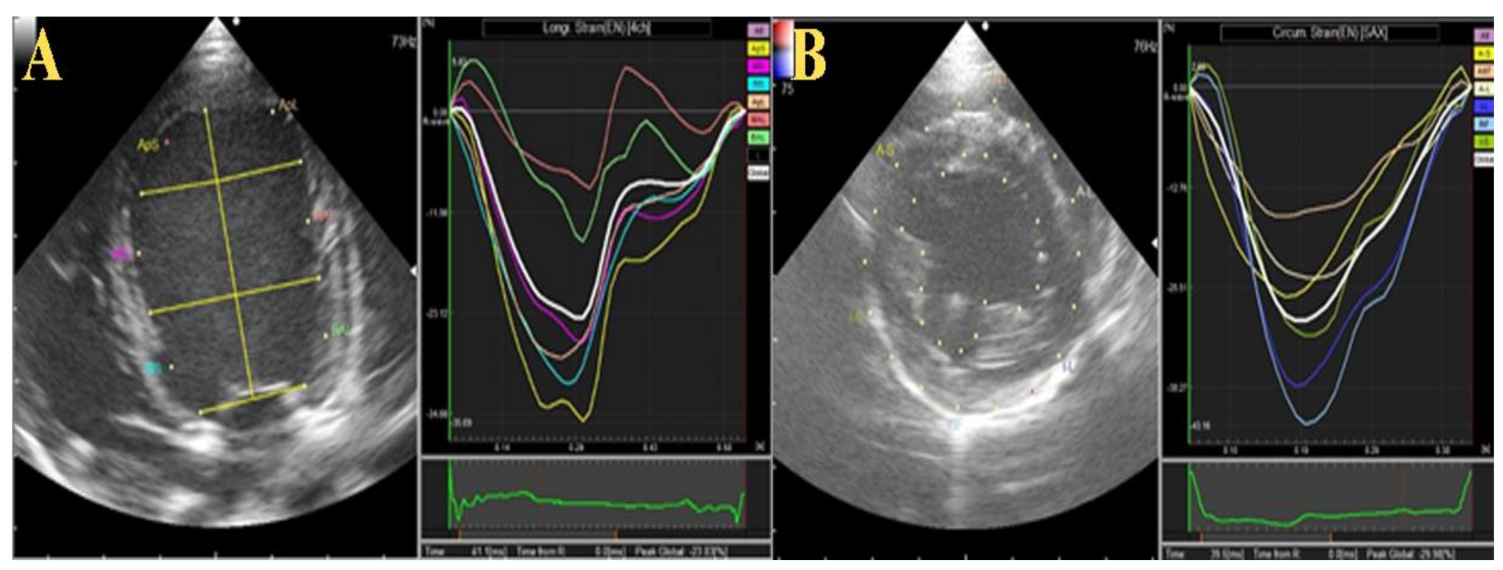

Figure 3. Schematic illustration of two-dimensional speckle tracking echocardiography (2DSTE) in the operated dogs. The entire left ventricular endocardium and epicardium were traced for measurement. (A) longitudinal strain was obtained from the left apical four chamber view. (B) circumferential strain obtained from short-axis view.

3.1.2. Two-Dimensional Speckle Tracking and Color M-Mode Echocardiography

Table 2 summarizes the 2D-STE (Figure 3) and CMME (Figure 4) data in the two operated dogs. The radial strain was increased in both dogs during the observation period. The total and basal IVPGs were only increased in the first dog at week 1 postoperative, then they reduced; meanwhile; in the second dog, the total and basal IVPGs remained higher than the baseline until week 4 post-operative. The mid-to-apical IVPGs were found to be elevated in the dog 1 until week 4 compared with the baseline; however, it was reduced in dog 2.

The 2D-STE was performed from the right parasternal short-axis view at the papillary muscle level and left parasternal apical four-chamber view. Digital cine-loops of three consecutive heart cycles with the frame rate set at 70–110 frames/s were captured from all dogs and saved as DICOM files for further processing using in-house code software (DAS-RS1 software 1.1v, Hitachi Aloka Medical). By using DAS-RS1, the short axis analysis and free use methods of video processing were used for short axis and long axis 2DSTE evaluation, respectively. The endocardium and the epicardium were outlined automatically at end-systole and end-diastole. The tracing borders were manually edited to ensure that the visualized real wall motion and the whole wall thickness were incorporated into the region of interest used in the frame-by-frame basis analysis. From the short-axis view, segmentation with an angular interval of 60° divided the LV into the following 6 segments; anterior, anterior septal, anterior lateral, inferior, inferior septal, inferior lateral. Based on tracing of these 6 segments, we reported the left ventricular global circumferential strain (GCS), global circumferential strain rate (GCSR) and global radial strain (GRS). From the left apical four-chamber view, longitudinal strain (LS) and longitudinal strain rate (LSR) were assessed [22].